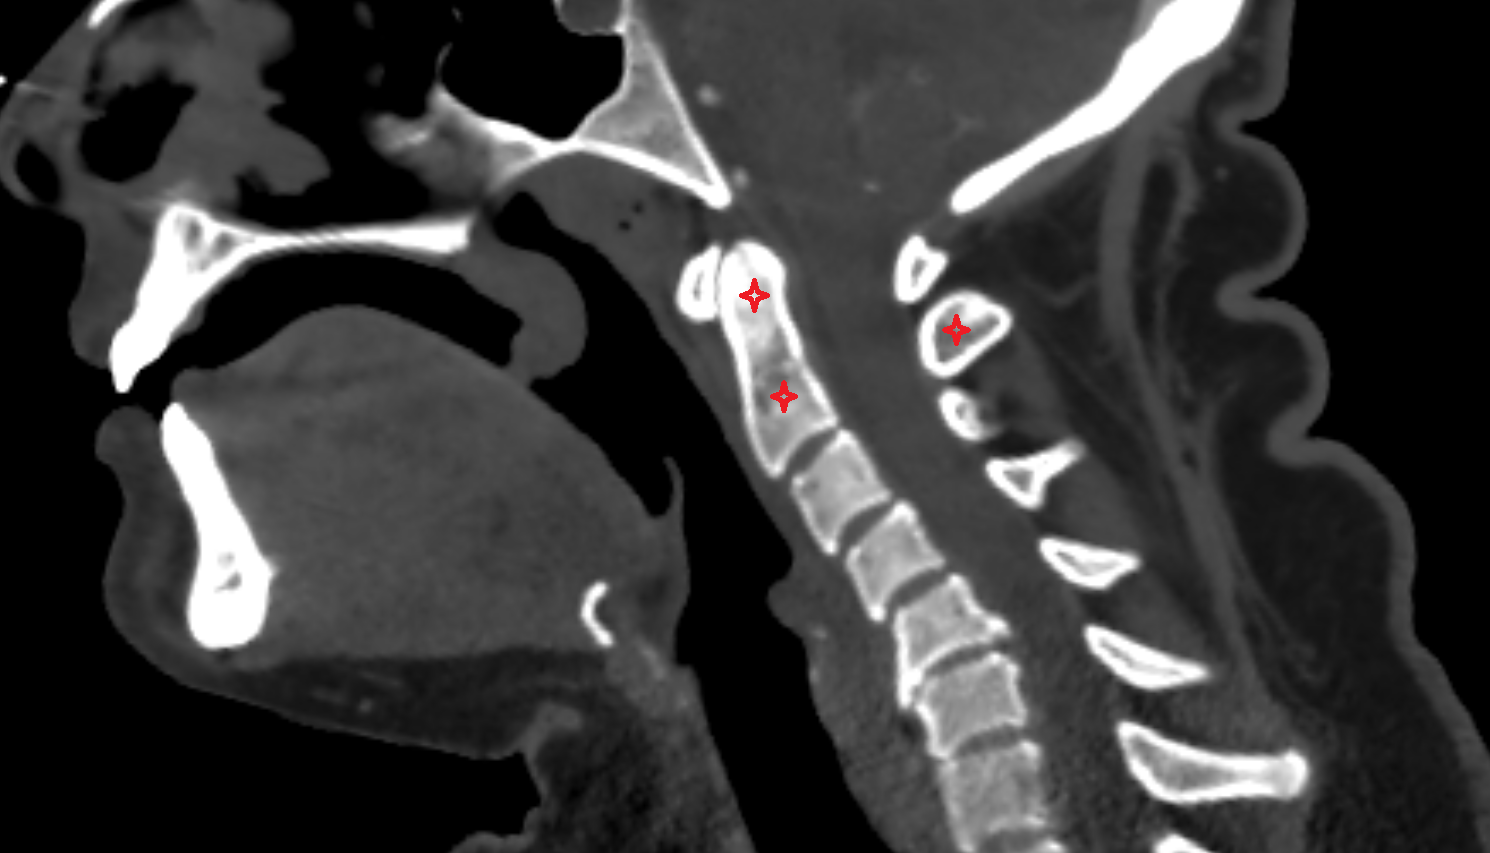

- Axis (C2 vertebra)

- C3–C4 intervertebral disc

- Anulus fibrosus of intervertebral disc

- Nucleus pulposus of intervertebral disc

- Anterior longitudinal ligament

- Posterior longitudinal ligament

- Ligamenta flava (Ligamentum flavum)

- Interspinous ligament

- Body of vertebra

- Intervertebral Disc